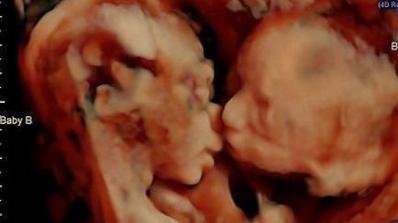

Невероятен момент беше заснет от 3D ултразвук с корема на бременна жена.

В утробата и двете и близначета се целуват, сподели Канал 3.

Забележителната фотография е направена в 25-тата седмица от бременността на Кариса Гил. Тя и съпругът й Ранди се чувстват благословени.